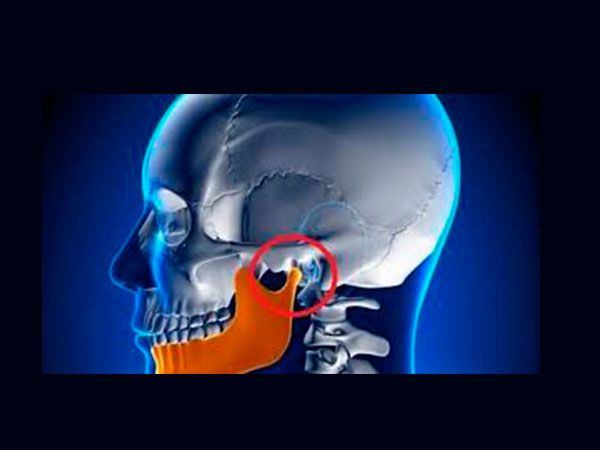

Articulación Temporomandibular / Dolor Miofascial

Bloqueo cerrado, desplazamiento de disco articular, artrocentesis, infiltración de toxina botulinica .